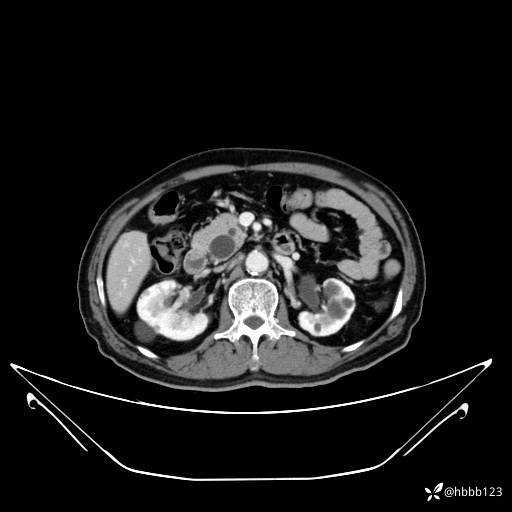

平扫: